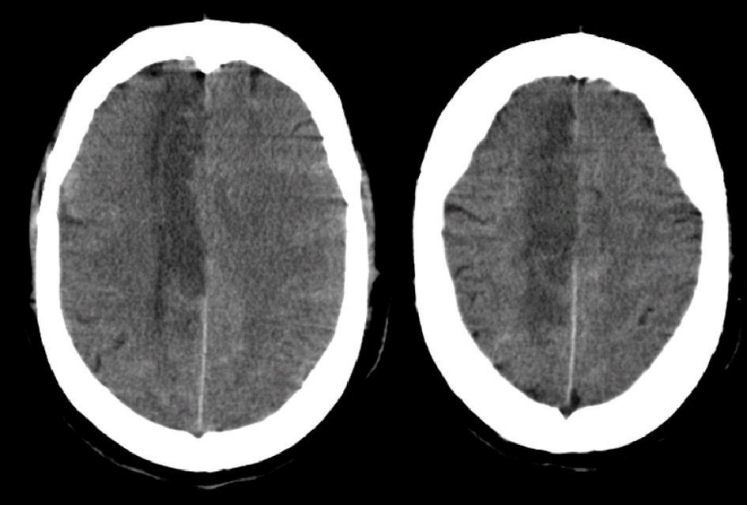

Outline the artery & pathology involved

ACA occlusion → Ischaemia